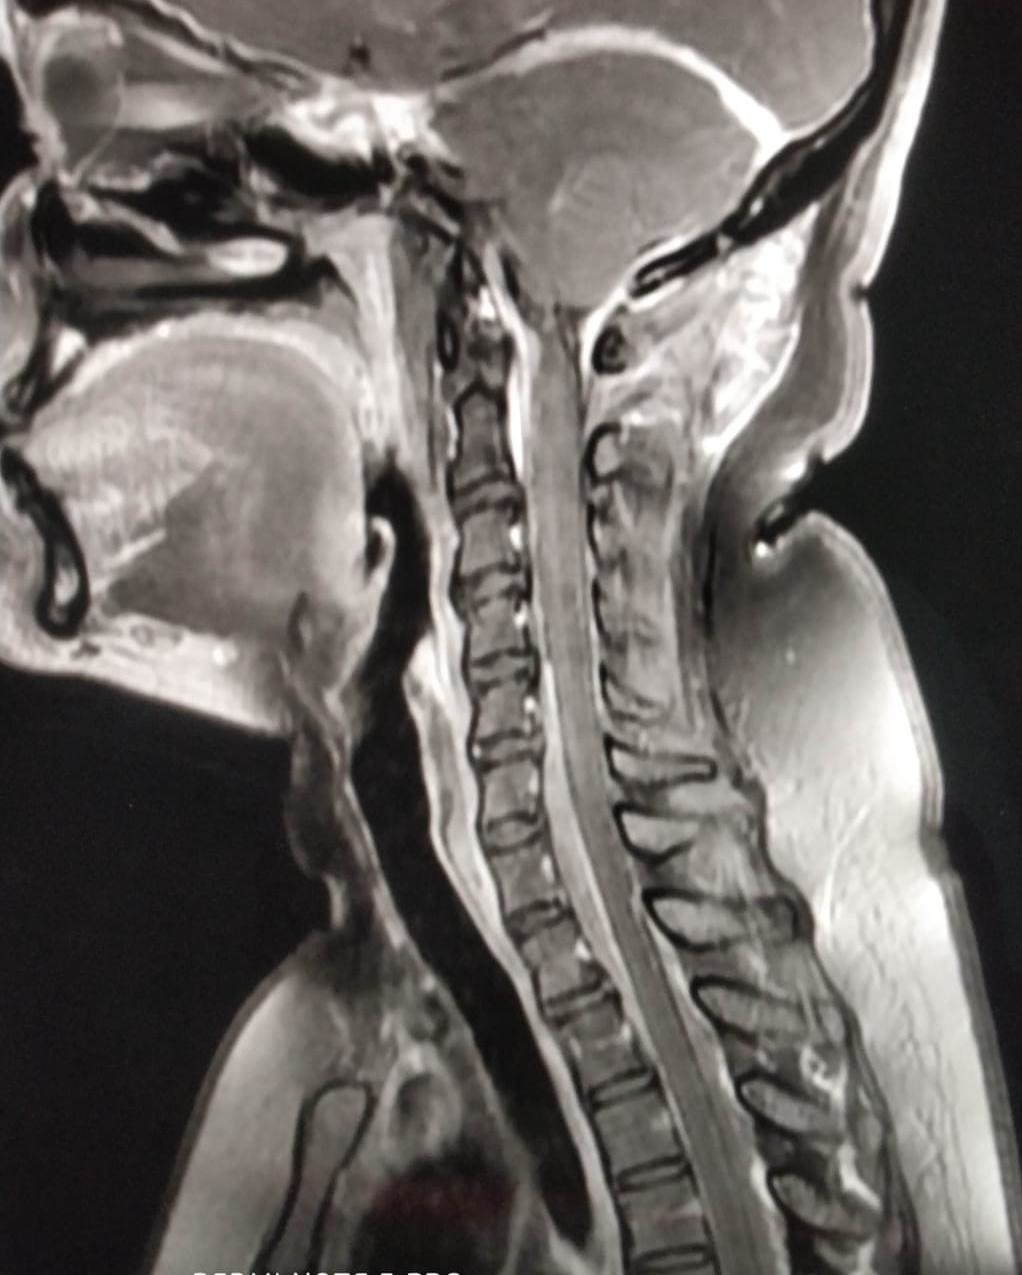

Click Here to View 1st X-Ray Image